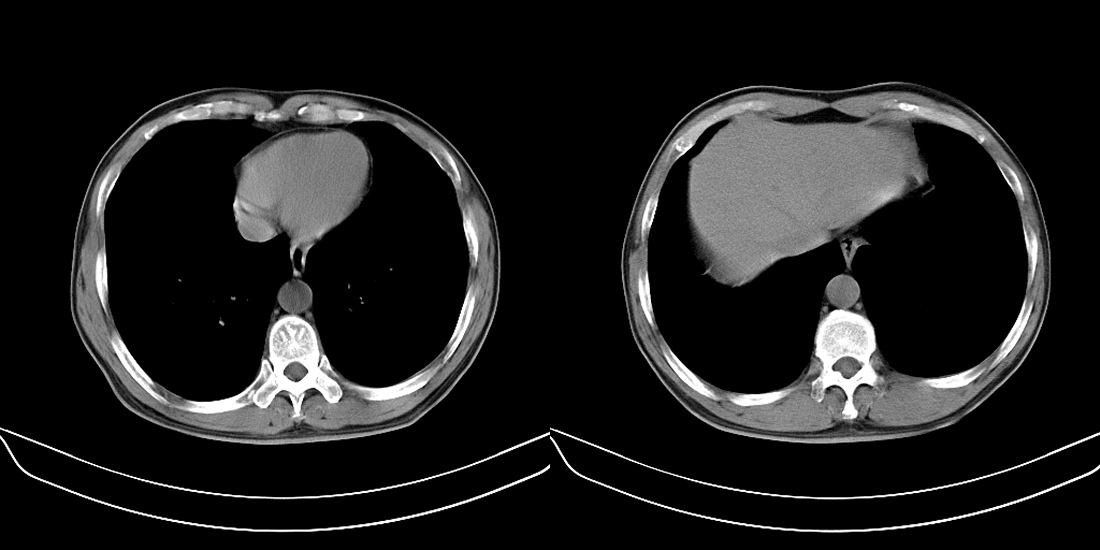

标题: CT10251:男性56岁,结核球? [打印本页]

标题: CT10251:男性56岁,结核球?

56岁男性,低热、消瘦,曾x线诊断肺结核。

两肺结核,左肺结核球。

双肺结核伴左上肺结核球形成

两肺多形性病变,支持肺结核.

两肺多形性病变,且在结核好发部位。支持肺结核.